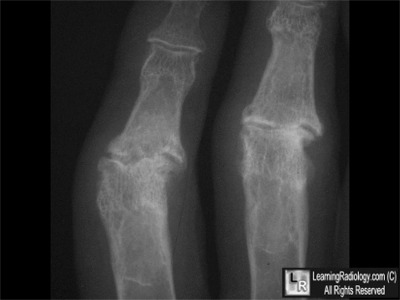

Case of the Week 495

What is the most likely diagnosis?

• 73 year-old woman with pain, redness, swelling in joints

Frontal Radiograph of Right Hand

Additional Images - Close-up View of PIP Joints

Close-up View of Proximal Interphalangeal Joints

Answer:

5. Erosive Osteoarthritis

Erosive Osteoarthritis

• Inflammatory arthritis which most commonly occurs in women over the age of 60

• It is a form of osteoarthritis with a strong inflammatory component

• Usually involves hand

• Hip and knee are rarely involved